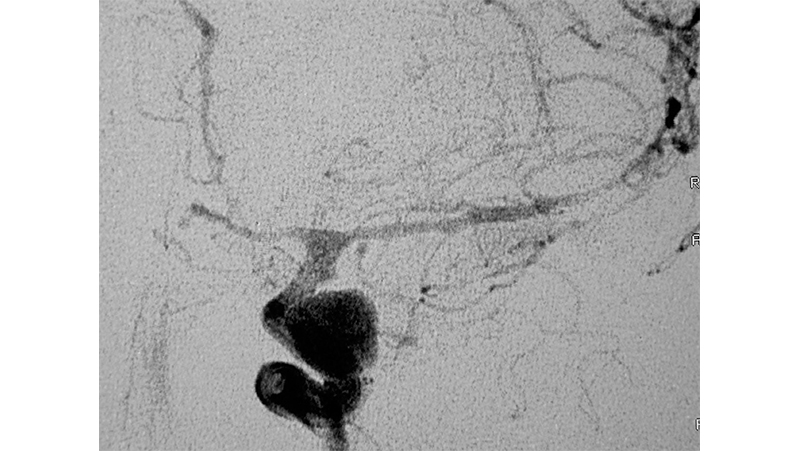

Εικόνα 2: Εμβολισμός και ασφάλιση του ραγέντος ανευρύσματος. Ταυτόχρονα χορηγήθηκε ενδαρτηριακά παπαβερίνη, με σημαντική βελτίωση του αγγειοσπάσμου και αύξηση του εύρους των αγγείων.